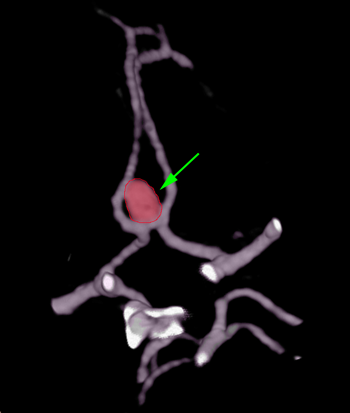

Aneurysm1

Ανεύρυσμα (περίγραμμα)